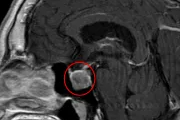

在医院做完一系列检查后,「脑胶质瘤」这个冰冷的诊断结果,如同一记重锤,将她打入了绝望的深渊。

她来到了美中爱瑞肿瘤医院。刚入院的小美,就像一个失控的「火药桶」,行为反常极了。一会儿吵着要吃药,一会儿急切地找医生治疗,一会儿又陷入极度的绝望,哭喊着不想活了,甚至连医生安排的核磁检查都拒不配合。她的反常不仅折磨着自己,也让家属心力交瘁。